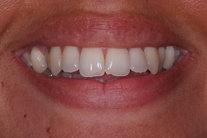

Tandreglering 1

Ung kvinna som tidigare haft tandreglering. Upplever inte att tänderna står i en fin tandbåge. 11 månaders behandling med genomskinliga Invisalignskenor resulterade i ett fint leende.